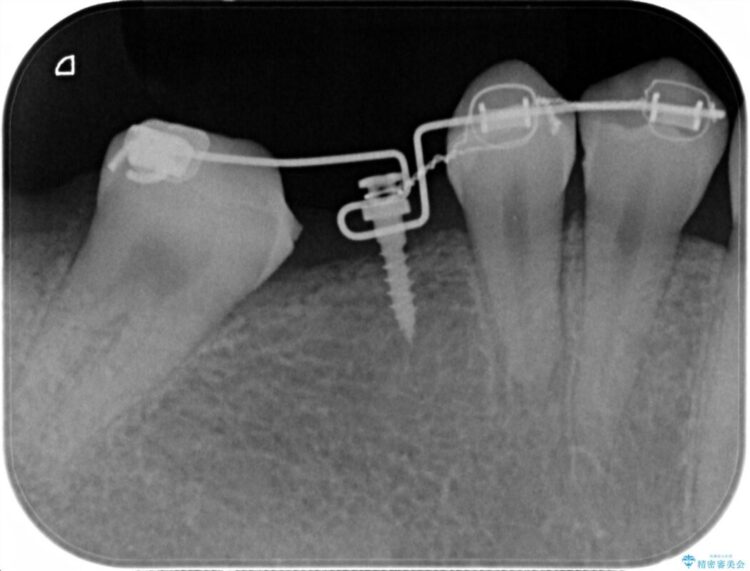

診査した結果、欠損した状態で長期間放置していたことが原因で最高峰の奥歯が欠けた部分に向かって傾斜してしまっていました。

この状態のままブリッジ治療へと進んでしまうと神経が露出する可能性が否定できないため、まずワイヤー装置による部分矯正で歯軸を通常位置へ戻してから補綴治療を行うこととしました。